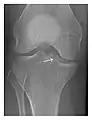

High-energy trauma fractures

Occult osseous injuries may result from a direct blow to the bone by compressive forces of adjacent bones against one another or by traction forces during an avulsion injury. Lesions in the tibial plateau, hip, ankle, and wrist are often missed. In a tibial plateau fracture, any disruption of the posterior and anterior cortical rims of the plateau should be sought. Impaction of subchondral bone will appear as an increased sclerosis of the subchondral bone (Figure 1). In the hip, posterior acetabular fractures also present subtle radiographic findings. The acetabular lines should then be carefully examined keeping in mind that the posterior rim, which is harder to see on X-rays, is more frequently fractured than the anterior rim (Figure 2). In the wrist, detection of carpal bone fractures is often challenging, with up to 18% of scaphoid fractures radiographically occult. Carpal fractures, especially the scaphoid, are associated with the risk of avascular necrosis. In apparently normal wrist radiographs from symptomatic patients, if there is history of a fall on an outstretched hand with pain in the anatomic snuffbox, suggesting scaphoid injury, the initial examination with posteroanterior, lateral, and pronation oblique views must be complemented by other specific views such as supination oblique and the "scaphoid" view A careful examination of cortices for evidence of discontinuity or offset and cancellous bone for lucency is necessary (Figure 3).[1]

Figure 1: A 56-year-old woman presenting with left knee pain after a fall. (a) Initial anteroposterior radiograph was considered normal, however, subtle cortical disruption of the anterior rim of the medial tibial plateau, medial to the tibial spine, is noted (arrow). (b) Coronal T1-weighted MRI confirms the cortical disruption (arrow) and shows extensive fracture through the proximal tibia. (c) Coronal proton density-weighted image with fat saturation shows extensive edema in the subchondral bone. Note also hypersignal adjacent to the medial collateral ligament corresponding to a grade I sprain (arrowheads).[1]